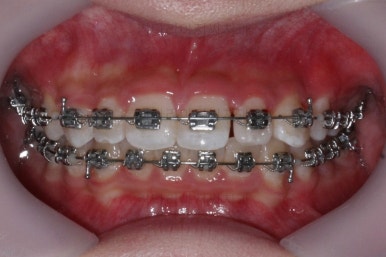

부산교정치과 키다리아저씨치과에서 치료한 이번 치료의 전후사진을 비교해 볼게요.

왼쪽이 치료 전, 오른쪽이 치료 후 모습입니다.

매우 복잡한 문제들을 복합적으로 가지고 있었던 경우였지만 만족할만한 결과를 얻을 수 있었어요.

이상 부산교정치과 키다리아저씨치과에서 치료한 왜소치, 과개교합, 매복치아 교정치료 사례였습니다.